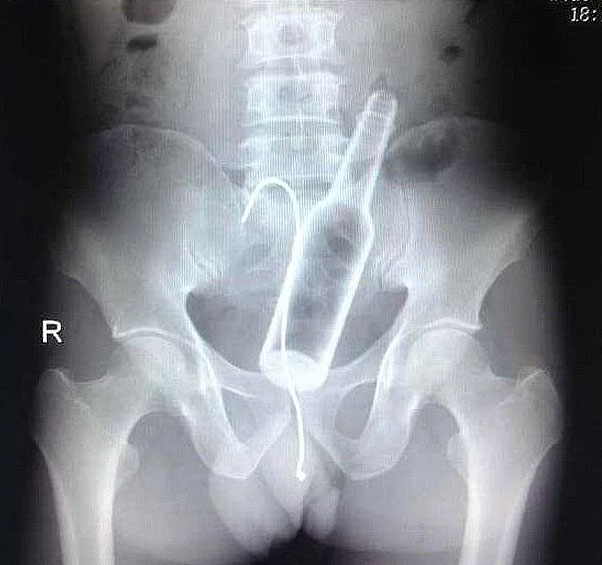

Röntgen filmlerinden "akıl almaz şeyler

Hastane koridorlarına düşenler bilir… Doktora görün, tahlilleri yaptır, röntgenleri çektir falan filan derken sayılmadan ömür gider. Gelin ki bu sefer ilginç şeyler çıkmış ki görün ağzımız açık kaldı…